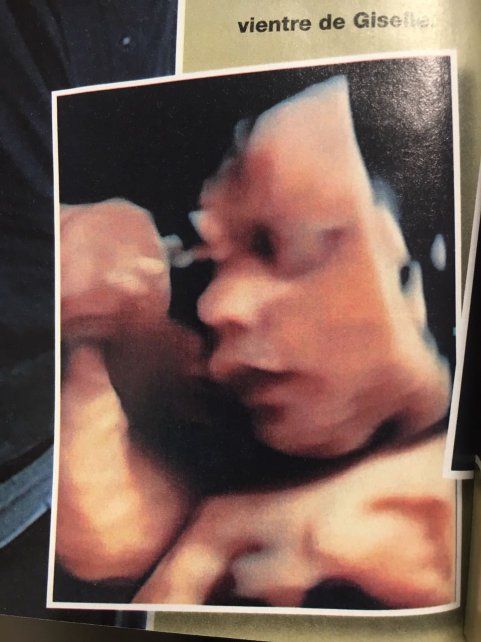

El exitoso empresario teatral mostró por primera vez en revista Gente las ecografías de su hijo y contó cómo fue el encuentro con la madre subrogada.

El artista, que espera a Dionisio para el 15 de abril, presentó a Giselle, la madre subrogada, y muestra por primera vez el rostro de su bebé en la última ecografía 4D.

En tanto, Flavio contó emocionado a revista Gente que "cuando me reuní con Giselle en Miami pude darle un beso en la panza, tocársela y me largué a llorar: sentí que en ese vientre estaba mi semilla".